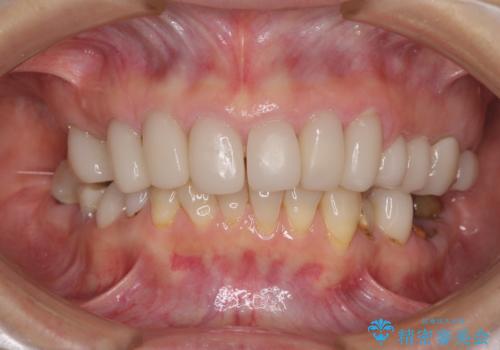

歯の欠損を放置 オールセラミックブリッジによる補綴治療

下顎には抜歯が必要な歯があったため、抜歯後に治癒を待ち、上顎とともにオールセラミックブリッジにて補綴治療を行うこととしました。

治療開始の日に欠損部も含めて仮歯が装着され、今までの不具合や不快感があっという間に改善されました。

抜歯部位の治癒を待つために時間がかかりましたが、来院回数は数回で済み、患者様には大変満足していただきました。